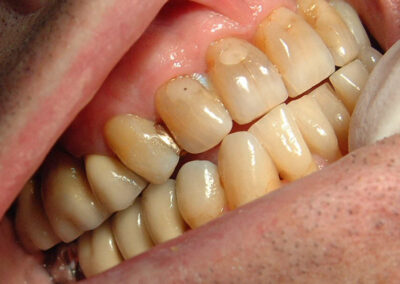

Bei der klinischen Untersuchung in habitueller Okklusion fällt die progene Stellung des Unterkiefers mit ausgeglichener Okklusion im Seitenzahnbereich auf den ersten Blick auf. Pathologische Kiefergelenksgeräusche sind nicht zu erheben.

Beachten Sie die als ausgeglichen imponierende habituelle Okklusion beiderseits im Seitenzahnbereich.

Deutlich beherdeter, devitaler 36 bei fehlendem 13 mit Lückenschluss.

Auffällig ist die umfangreiche, technisch sehr ordentliche, im Laufe der vielen Jahre durch verschiedene Behandler in Teilen mehrfach erneuerte prothetische Versorgung in allen 4 Quadranten. Die in der Folge von Knochenabbau „langen Zähne“ im Oberkiefer-Seitenzahnbereich bei Abwesenheit entzündlicher Taschen und guter Mundhygiene sind deutliches Zeichen funktioneller Überlastung. Die Versorgung des rechten Unterkieferquadranten weisen zumindest einen der Vorbehandler als Könner der Zahnerhaltung im Grenzbereich auf. Vor diesem Hintergrund ist es besonders überraschend, dass der inzwischen 65jährige Patient ganz offensichtlich nicht ein einziges Mal gründlich zahnärztlich untersucht worden ist. Aufgrund von lingualer Sekundärkaries an den wichtigen Pfeilerzähnen 46 und 47 war die Indikation zur Neuversorgung des 4. Quadranten vom letzten Vorbehandler bereits gestellt worden.